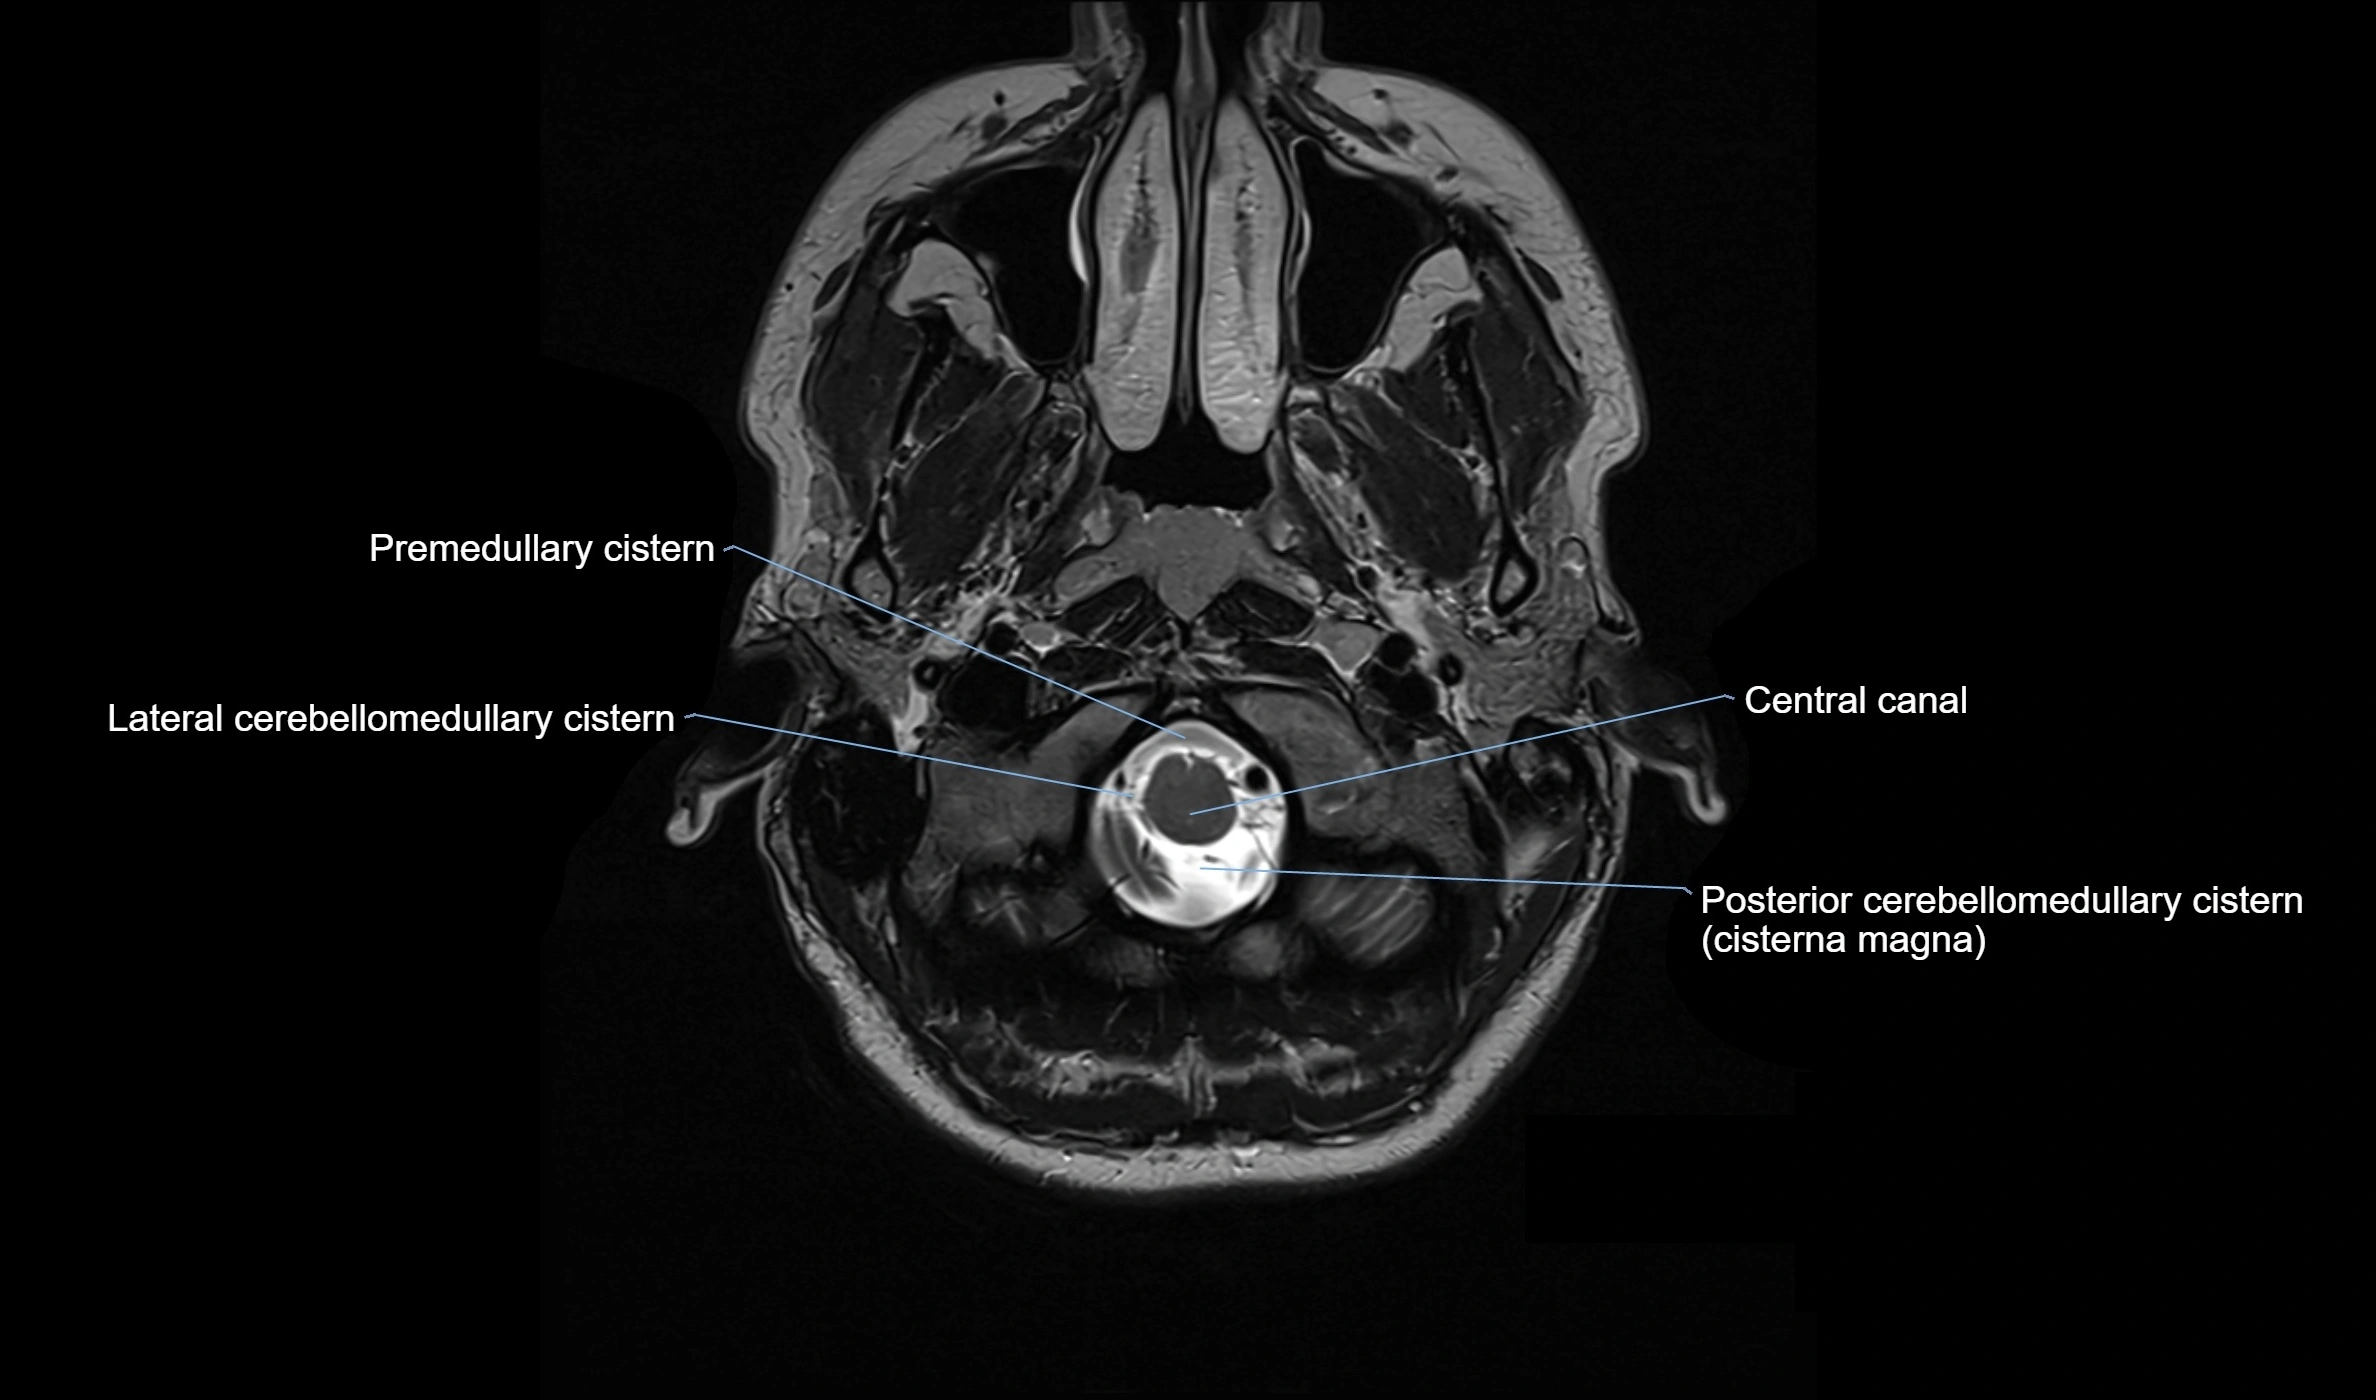

Ambient cistern

The ambient cistern is a paired, narrow, and elongated subarachnoid space located bilaterally along the lateral aspect of the midbrain. It serves as a conduit between the interpeduncular cistern anteriorly and the quadrigeminal cistern posteriorly. This cistern houses critical neurovascular structures, including parts of the posterior cerebral artery, superior cerebellar artery, trochlear nerve (cranial nerve IV), and the basal vein of Rosenthal. It plays an important role in the circulation of cerebrospinal fluid (CSF) and provides an anatomical corridor for various vessels and nerves passing around the midbrain.

MRI Appearance

• T2-weighted images:

• The cistern is hyperintense (bright) due to the high water content of CSF.

• Encapsulated vessels and nerves are seen as flow voids or hypointense lines within the bright background.